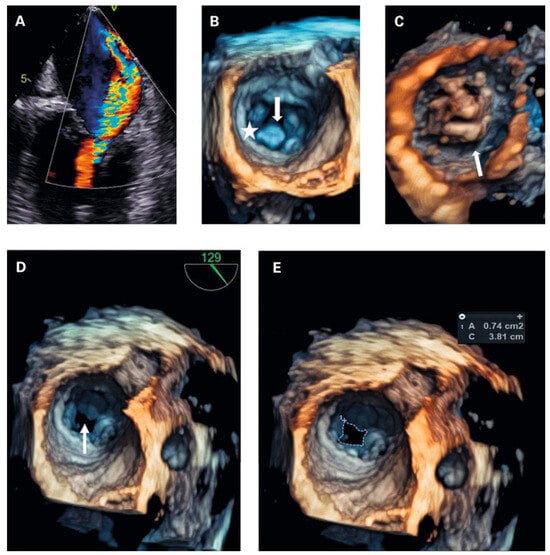

Figure 4. (a) transoesophageal echocardiography (tOe, 30°): Colour doppler revealed severe mitral regurgitation, which was not apparently visible in transthoracic echocardiography. (B) 4d tOe (surgical view at diastole) showing normal valve orifice at valvular level. Arrow subvalvular thickening. Asterisk posterior mitral valve annulus. (C) 4d tOe (ventricular view at diastole) visualising extensive thickening of the subvalvular apparatus as cause of stenosis. (D) 4d tOe surgical view of stenotic mitral valve area (arrow). (e) 4d tOe planimetry of mitral valve area from surgical view.

To exclude left-heart disease as a possible cause of the congested bronchial vessels and the alveolar haemorrhage syndrome, first transthoracic and later transoesophageal echocardiography were performed. The main finding was a grotesque doming of thickened mitral leaflets with a severe subvalvular mitral stenosis (transthoracic echocardiography figure 3A–F and transoesophageal echocardiography figures 4A–D; mean pressure gradient 16.2 mm Hg, reference <5 mm Hg, at a heart rate of 82/min, calculated mitral valve area by pressure half-time method 1.3 cm2, reference >1.5 cm2; figure 3f; planimetry of mitral valve area 0.74 cm2 in TOE approach, figure 4d+e) and severe mitral regurgitation with pulmonary vein backflow due to restricted leaflet motion (fig. 4a). The right ventricular / right atrial pressure gradient across the tricuspid valve could not be obtained.

Transthoracic and transoesophageal 4D imaging revealed extensive fusion of thickened and shortened chordal structures extending down to the papillary muscles, a shortened posterior leaflet and a prolonged and entirely thickened anterior leaflet with restricted mobility, and mild calcification (fig 3 and fig 4), adding up to a Wilkins Score of 13 points (range 4–16).